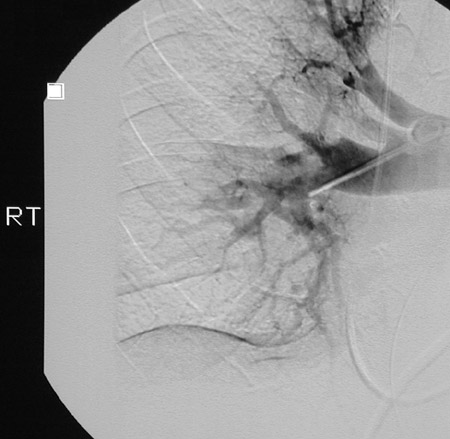

These views follow thrombolysis with an angiogram in a patient with multiple pulmonary thromboemboli. Note that there is increased filling compared to the prior set of images. There is still some delay in filling

toward the lower lung

.